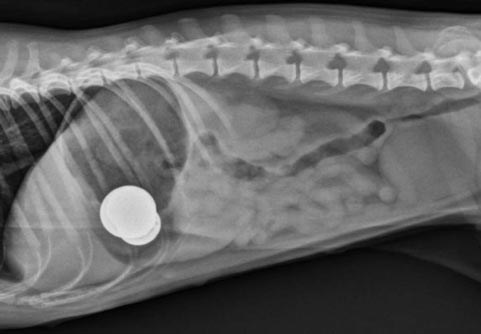

Mineral seng merupakan salah satu mineral yang sangat penting untuk pemeliharaan tubuh, akan tetapi dalam tingkatan tertentu (asupan sangat tinggi/terlalu banyak), mineral tersebut dapat berbahaya dan bisa menyebabkan keracunan pada semua jenis anjing.Penyebab penyakit :